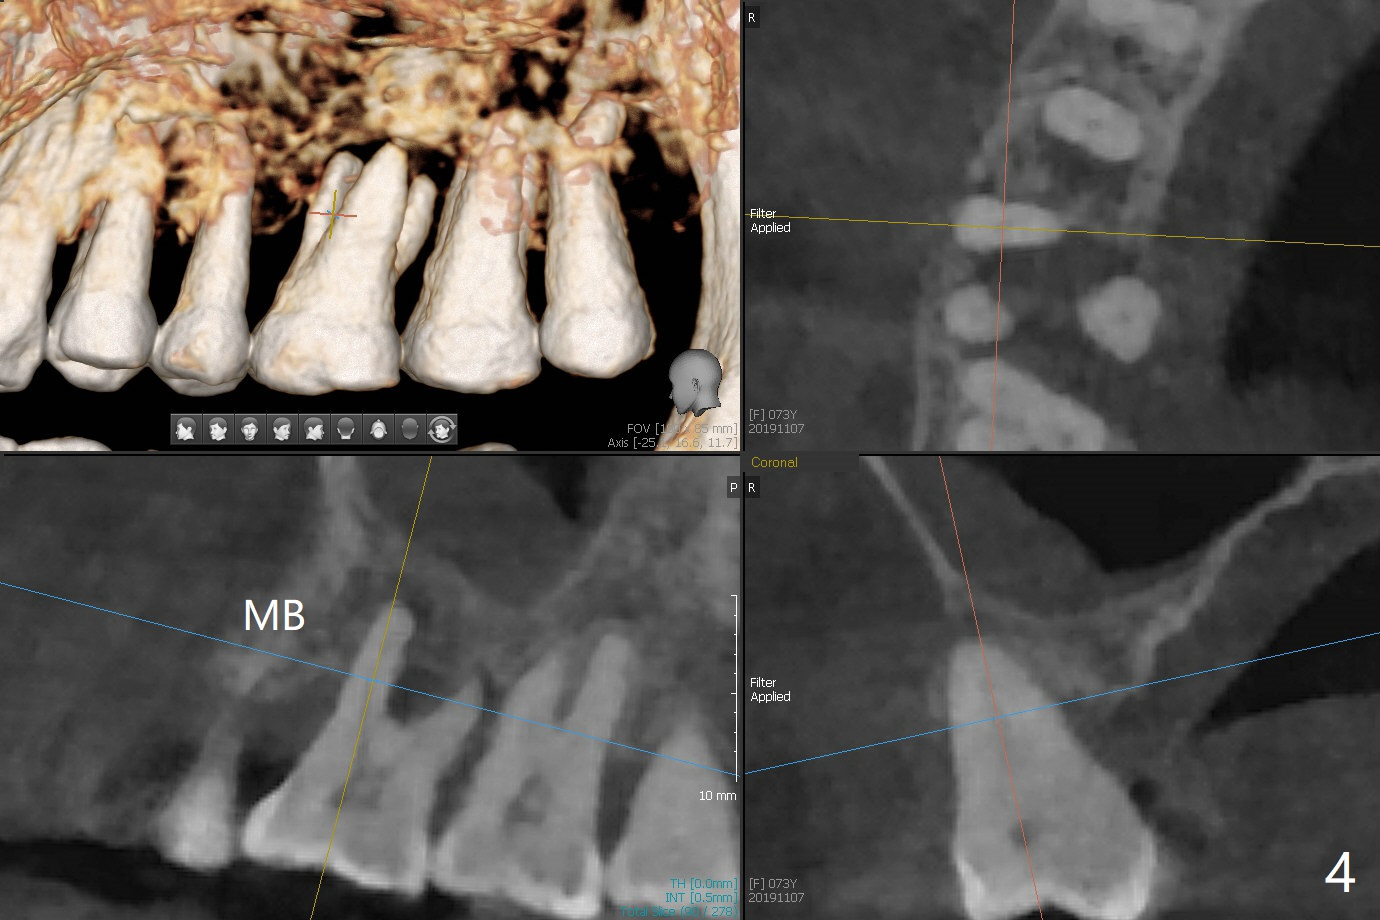

A 73-year-old woman with controlled diabetes has cold and hot sensitivity of the tooth #3. Although the bone loss is striking (Fig.1), mobility is I with the deepest pocket DL ~6 mm. Endo ice induces pain. Extraction and guided immediate implant appears to be the best option (Fig.2 (5x7mm FC)). Note the bone height (2.9 mm) and the thick sinus membrane (M, Fig.2') . B: buccal. Bony defect will be filled with sticky bone and held in place with Cytoplast, while PRF for sinus lift. Because she is afraid of implant, RCT, followed by SRP and possibly periodontal surgery, seems to be viable because of the straight, not-so-narrow canals (Fig.3-5). Due to time constraint, immediate implant will be done free hand. Use IS cassette, since there are 3 and 4 mm stoppers. Prepare FC dummy and water lifter for sinus lift.